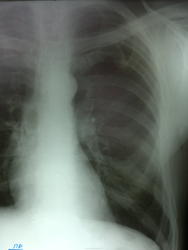

Качество рентгенограммы плохое (с негатоскопа). Дообследование после флюшки - тень слева. Пациента не видел, запросил амбулаторную карту. По карте с 2011 года ни ФЛГ, ни рентгенографии не проходил

Сделан бок - норма. В 2011 году ножевое ранение грудной клетки - которое пациент лечил дома, без обращения за медицинской помощью. В проекции левой ключицы и в/3 грудной клетки слева грубые келлоидные рубцы.

Костная перемычка между I и II рёбрами. Подозреваете что-то ещё - укладка по Флейшнеру.

Подумал сразу о костной пермычке, но смутило то, что на ФЛГ за 2010 год было без патологии.

Еще I межреберье слева, в два раза больше чем справа.

Бок сделаю завтра. А травмы 100% были, консолидированные ребра слева